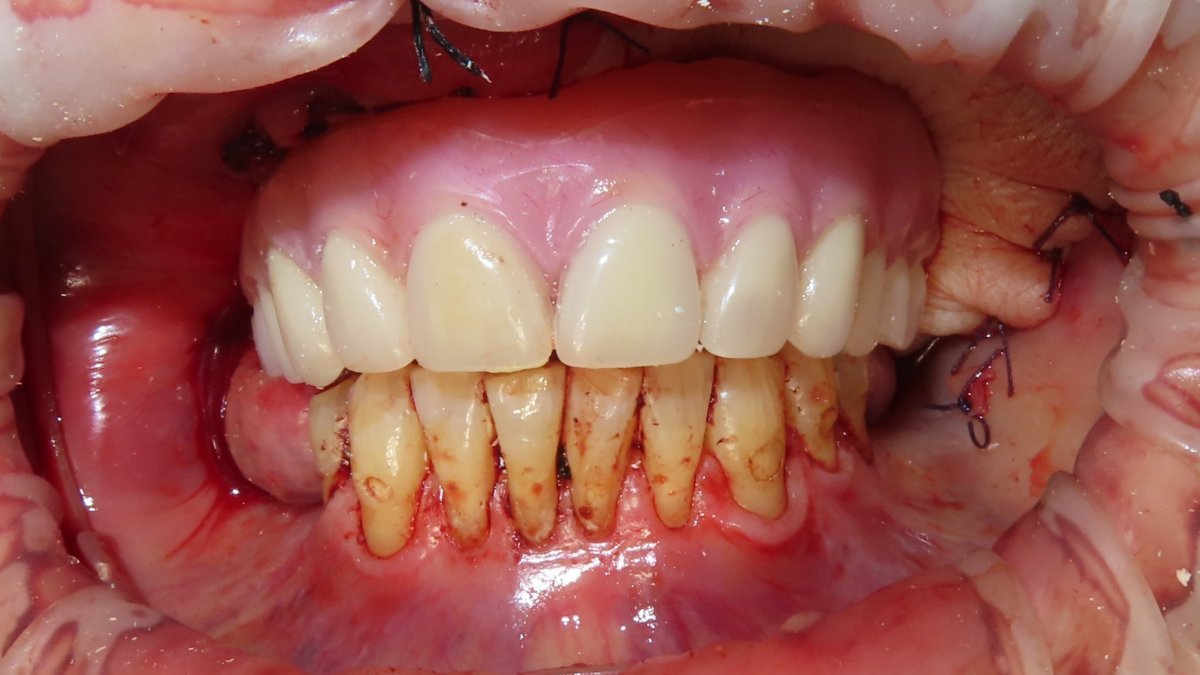

Pre-op